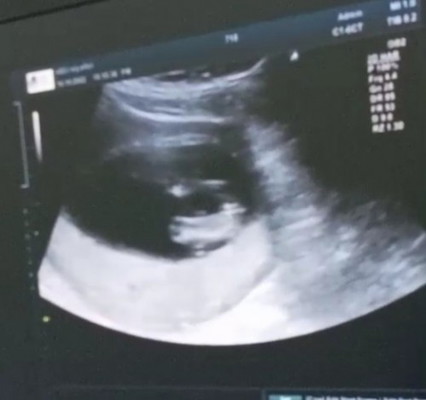

แบบนี้ลูกสาวใช่ไหมคะ แม่ๆ เครื่องหมาย = ช่วยแม่ยืนยันอีกเสียงหน่อยค่า ☺️💕

น่าจะใช่ค่ะแม่เพราะไม่มีไข่หรืออะไรยื่นออกมาค่ะ